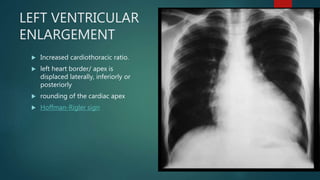

LEFT VENTRICULAR

ENLARGEMENT

 Increased cardiothoracic ratio.

 left heart border/ apex is

displaced laterally, inferiorly or

posteriorly

 rounding of the cardiac apex

 Hoffman-Rigler sign